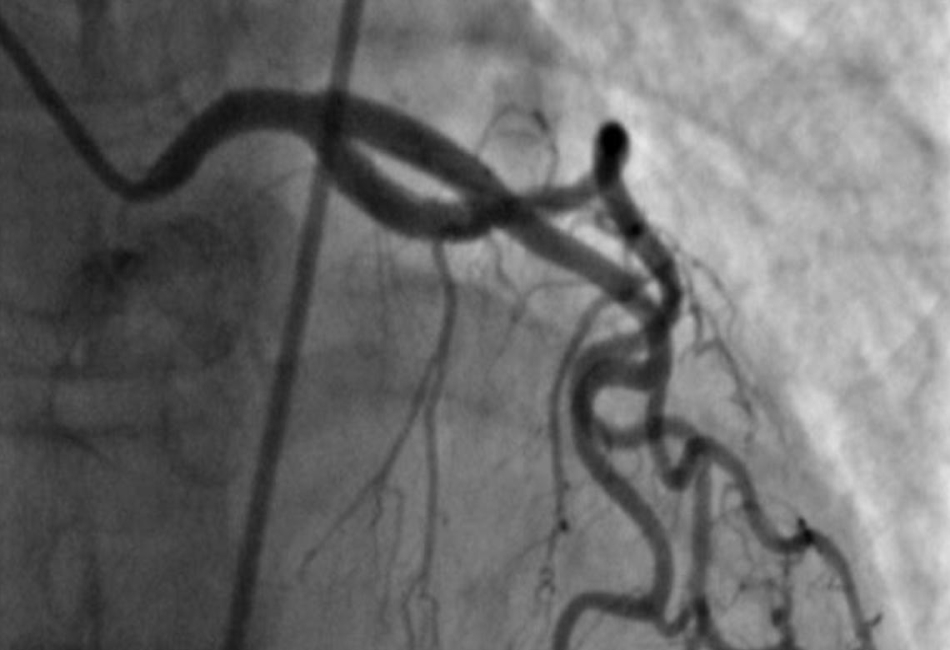

In these cases, courts rely on expert opinions to identify deviations from accepted medical guidelines. This involves assessing pre-procedure diagnostics, such as stress tests, imaging studies, or lab results, and examining whether they supported the medical decision. For example, a cardiologist may testify if results of an angiogram or echocardiogram were misinterpreted or manipulated to justify a procedure.